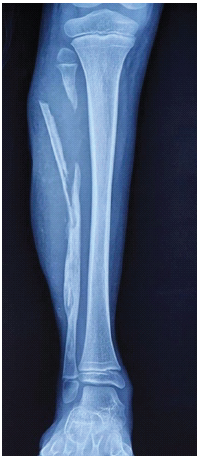

A Rare Case of Chronic Pan-Diaphyseal Osteomyelitis of the Fibula in a Child Treated by Near Total Fibulectomy: A Case Report

Venkataramana Kuruba , Elandevan Gunasekaran , Vignesh Chandrasekar , Nataraj Agrahara Rangashamaiah , Showry Abraham , Sabaricharan Shanmugam

………………………………p.247-251